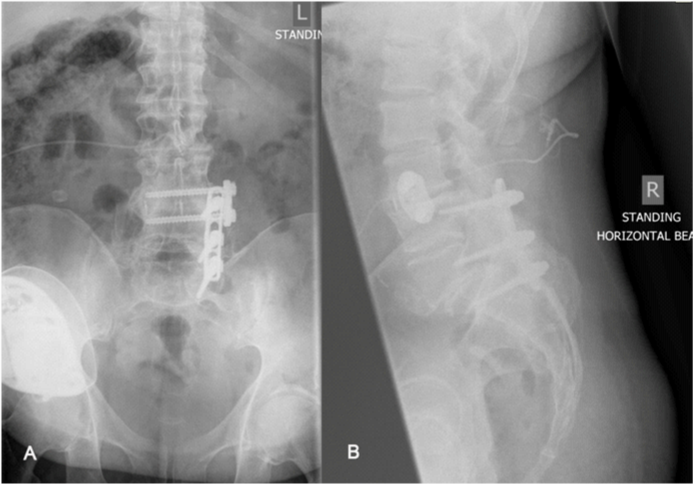

On presentation patient confessed and accepted the fact that he could never been pain free but stated on the top of his normal back and leg pain he had developed a much worse back pain just above his normal pain. He stated that the pain on his back had significantly worsened over the last 2 years as opposed to his leg symptoms that had remained unchanged. On examination, he was an obese gentleman with slightly positive saggital balance and a long posterior lumbar surgical scar. There was also an intrathecal morphine pump in his left loin. Neurological examination was unremarkable apart from knee reflexes been diminished bilaterally. Plain x-rays confirmed the presence of intrathecal catheter and implants were remaining intact and in situ and also demonstrated some evidence of L4-S1 bony fusion (Figure 1), which was further confirmed with CT scan. At L3-L4 level it demonstrated disc space narrowing and endplate sclerosis suggestive of adjacent segment disease requiring further imaging investigations. An MRI scan of the lumbasacral spine showed severe degeneration of the L3-L4 disc (adjacent level to previous fusion) with associated lateral recess stenosis impinging the left L2 and the right L3 nerve roots (Figure 2).

Figure 1 A) AP view lumbar spine demonstrating presence of intrathecal catheter and implants remaining intact and in situ with some evidence of L4-S1 bony fusion. B) Lateral view of lumbar spine demonstrating L3-L4 disc space narrowing and endplate sclerosis suggestive of adjacent segment disease.